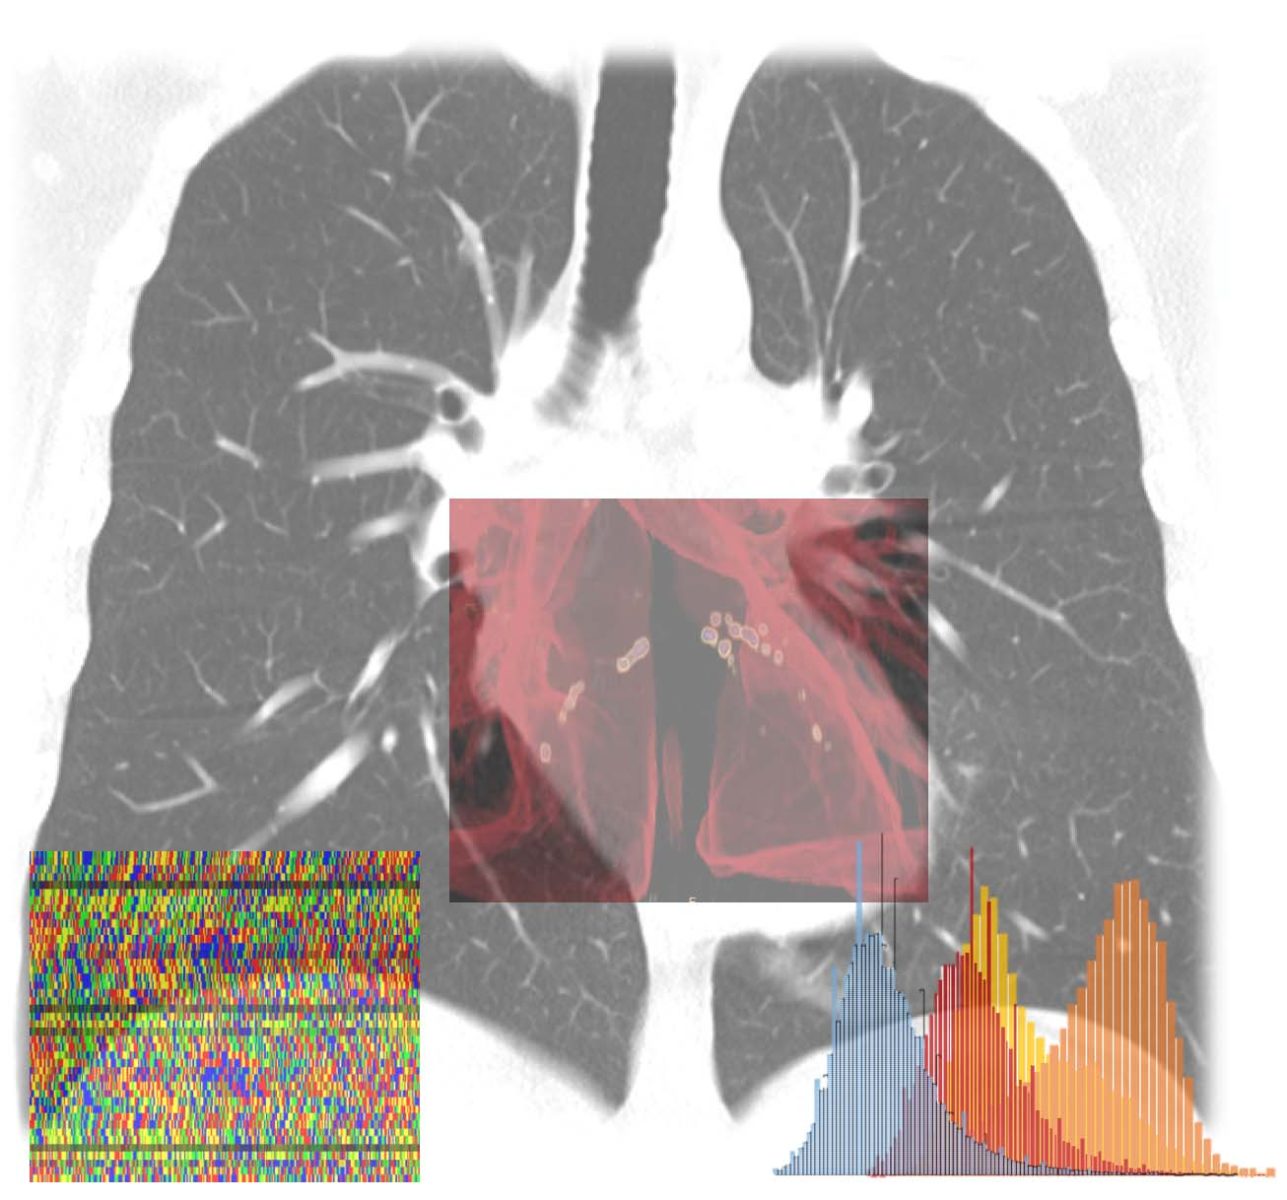

L’obiettivo del progetto è duplice: da un lato riconoscere nella popolazione generica le persone a maggior rischio di sviluppare le forme gravi di Covid-19 se infettate dal virus, quelle da proteggere maggiormente; dall’altro riconoscere tra i pazienti che mostrano i primi sintomi da Covid-19 quelli che avranno la prognosi peggiore. Il progetto partirà da questo secondo obiettivo, con un algoritmo AI che integrerà immagini diagnostiche, parametri clinici e di laboratorio, stato infiammatorio, e profilo genetico del paziente e del virus.

Il progetto prevede tre fasi principali: una prima fase di raccolta e omogeneizzazione dei dati di oltre 2000 pazienti ricoverati nelle scorse settimane e di cui si conosce la prognosi; una seconda fase di sviluppo e implementazione dell’algoritmo, che verrà “allenato” per imparare a combinarli in modo “intelligente” per predire il rischio del singolo paziente, e una terza fase di test e validazione del prodotto su una seconda coorte di pazienti e in eventuali studi prospettici.